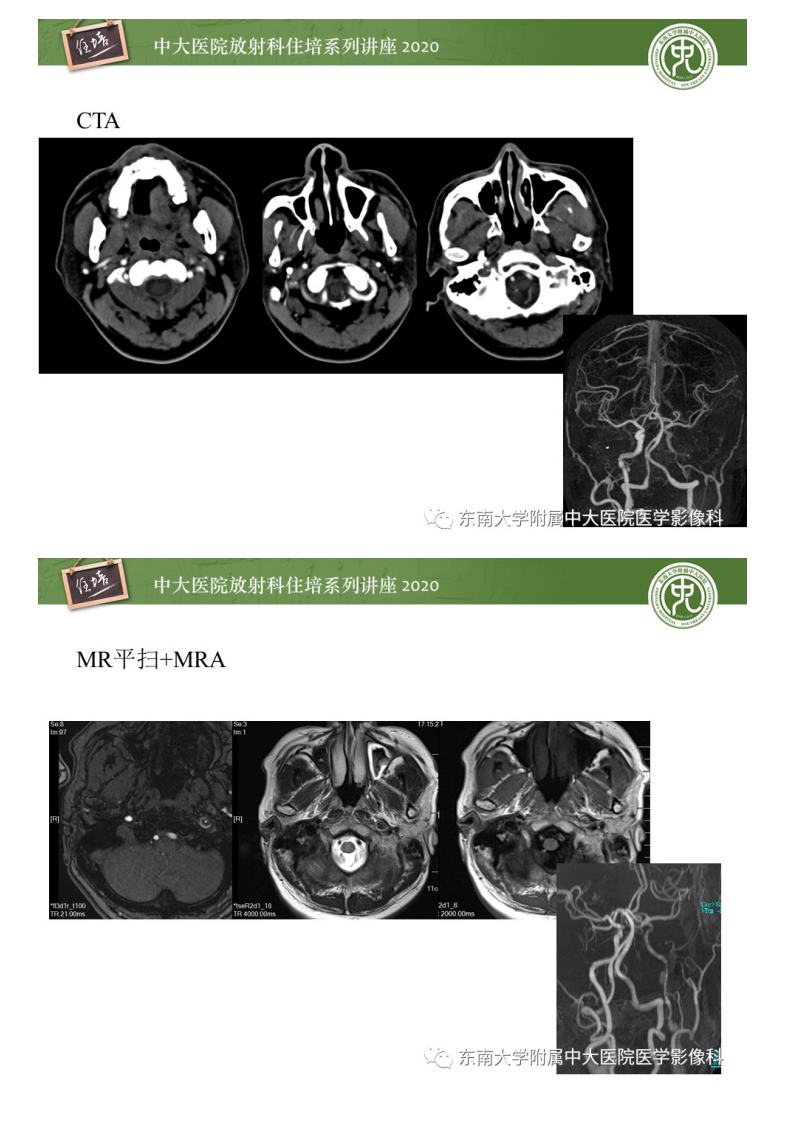

20200419_1【中大放射住培系列讲座】颈动脉夹层及夹层动脉瘤的影像诊断及评估.pdf